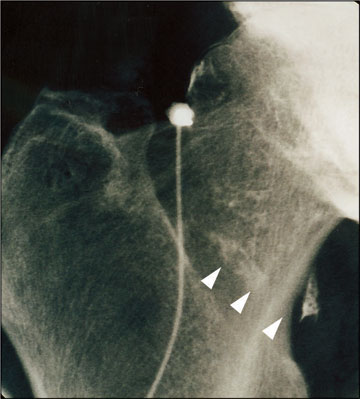

Rheumapatienten, bei denen einzelne Gelenke besonders schwer betroffen sind, können vom Verfahren der Radiosynoviorthese profitieren. Bei dieser nuklearmedizinischen Therapie wird ein Radiopharmakon direkt in das schmerzende, ruhiggestellte Gelenk gespritzt. Dort zerstört es die Zellen der wuchernden, entzündeten Gelenkinnenhaut (Synovia), die die Schmerzen verursacht. Zum Einsatz kommen dabei radioaktive Substanzen (Beta-Strahler), deren Strahlung im Gewebe nur eine Reichweite von wenigen Millimetern hat. Dadurch bleibt die Wirkung auf die entarteten Zellen der Gelenkinnenhaut beschränkt. Das umliegende Gewebe wird nicht geschädigt. Die Radiosynoviorthese kann, sollte die Gelenkinnenhaut erneut wuchern, problemlos wiederholt werden. |